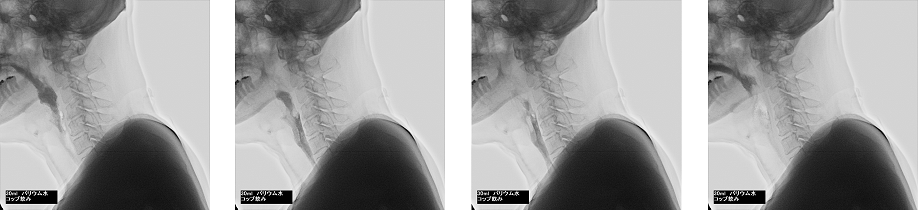

嚥下造影検査

嚥下造影検査(VF:Videofluoroscopy xamination of swallowing)は、バリウムを混ぜた食べ物や液体を実際に飲み込んでいただき、嚥下機能を評価する検査です。動画として診療科に提供しています。